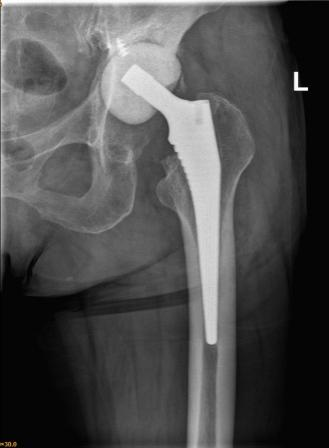

经过前期的治疗,现在左侧髋关节疼痛是影响李大妈生活质量的最大问题。通过对本次入院后髋关节CT的再次评估,张海军主任发现患者左侧髋臼骨缺损比3月前明显增多,普通假体无法完成手术,决定采用3D打印新技术评估髋臼缺损、模拟手术方案,经过3D打印模型和计算机测量评估,决定使用钽金属垫块和多孔钽杯重建髋臼。

依赖于术前准备充分,本例复杂髋关节翻修术不到2小时顺利结束。手术的顺利给了李大妈极大的信心,对她来讲,最大的心愿就是能尽快下地行走,我们团队为她量身定制个体化康复方案,经过几天的康复训练,李大妈生活基本自理,可以扶拐恢复行走,相信肌肉力量恢复后,李大妈回归正常生活的愿望很快就能实现!